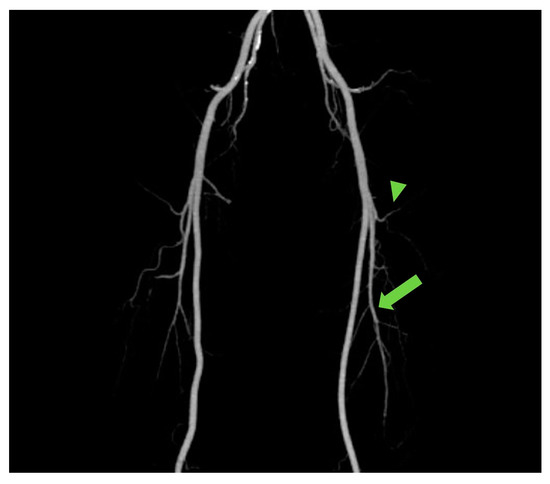

The ALT free flap is reliable and versatile owing to the appropriate diameter of its vascular pedicle and harvestability as a “freestyle flap”. In addition, it enables two-team approaches in the head and neck region, which can shorten the total operation time [8,9,10,11,12]. However, despite these advantages, there are clear drawbacks such as muscle-penetrating musculocutaneous perforators, and the varied branching pattern of LCFA, resulting in time-consuming dissection [13]. To overcome these hassles, the anatomical studies of branching patterns among ethnicities have been conducted [10,11,14], such knowledge regarding anatomic variation of the branching patterns potentially aiding planning and flap harvesting. However, with CTA, the branching pattern of each individual’s LCFA can be seen at a glance in maximum intensity projection (MIP) [15] (Figure 4). Moreover, CTA can provide individualized information regarding the location, number, length, and course of perforators in each patient, actually aiding in planning and designing the reconstruction and harvesting of the flap [6,16].

Figure 4.

The maximum intensity projection (MIP) reconstruction showing the anatomy and course of perforators from transverse branch (arrowhead) and descending branches (arrow).